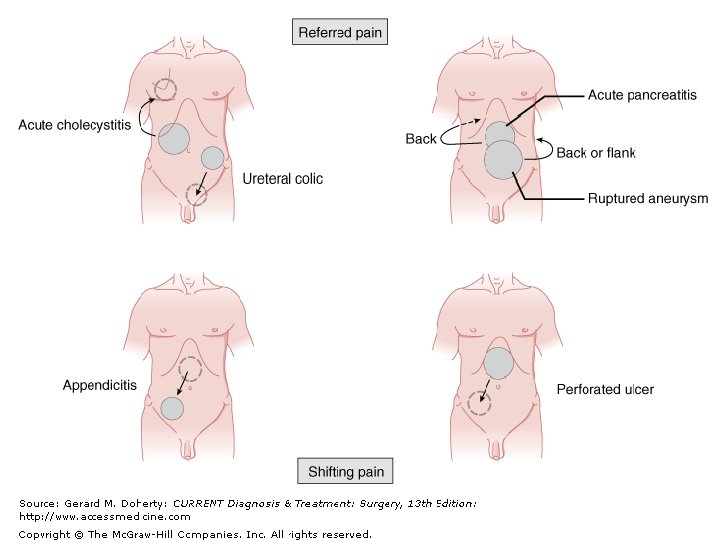

KUJDES!!!!! • MI- Dhimbje epigastrike • Pneumonia- Dhimbje ne abdomenin e siperm